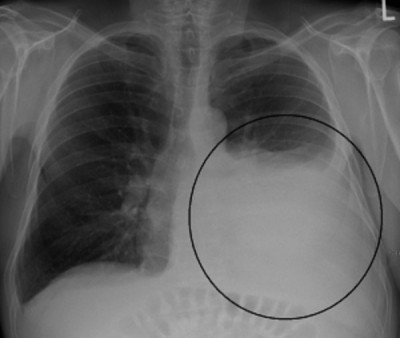

Ho ra máu do ung thư

Ho ra máu là tình trạng khạc ra máu trong và sau khi ho, máu ra ngoài bằng đường miệng hoặc mũi do tổn thương từ thanh quản trở xuống. Chẩn đoán ho ra máu do ung thư thường đơn giản, tuy...